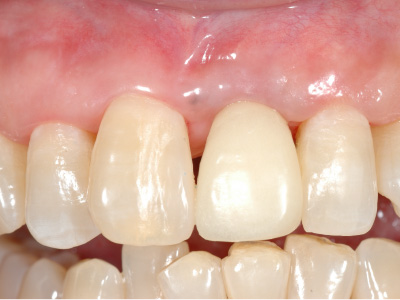

この時点では、歯と歯の間の「歯間乳頭」と呼ばれる歯茎が不足しているため隙間が空いており、インプラントの被せ物がいかにも人工物のように感じるため、審美的な仕上がりとはいえない。

そこで、上顎から切り取ってきた歯茎をインプラント周りに移植し、歯茎に厚みを持たせます。

歯茎の移植によって歯茎の隙間が埋まり、より自然な見た目を実現できました。

最終的に、周りの歯の色と形に調和するセラミックの被せ物をインプラントにセット。

歯茎との間に隙間がありませんし、色形のみでなく、すべてにおいて審美的に優れた仕上がりとなりました。